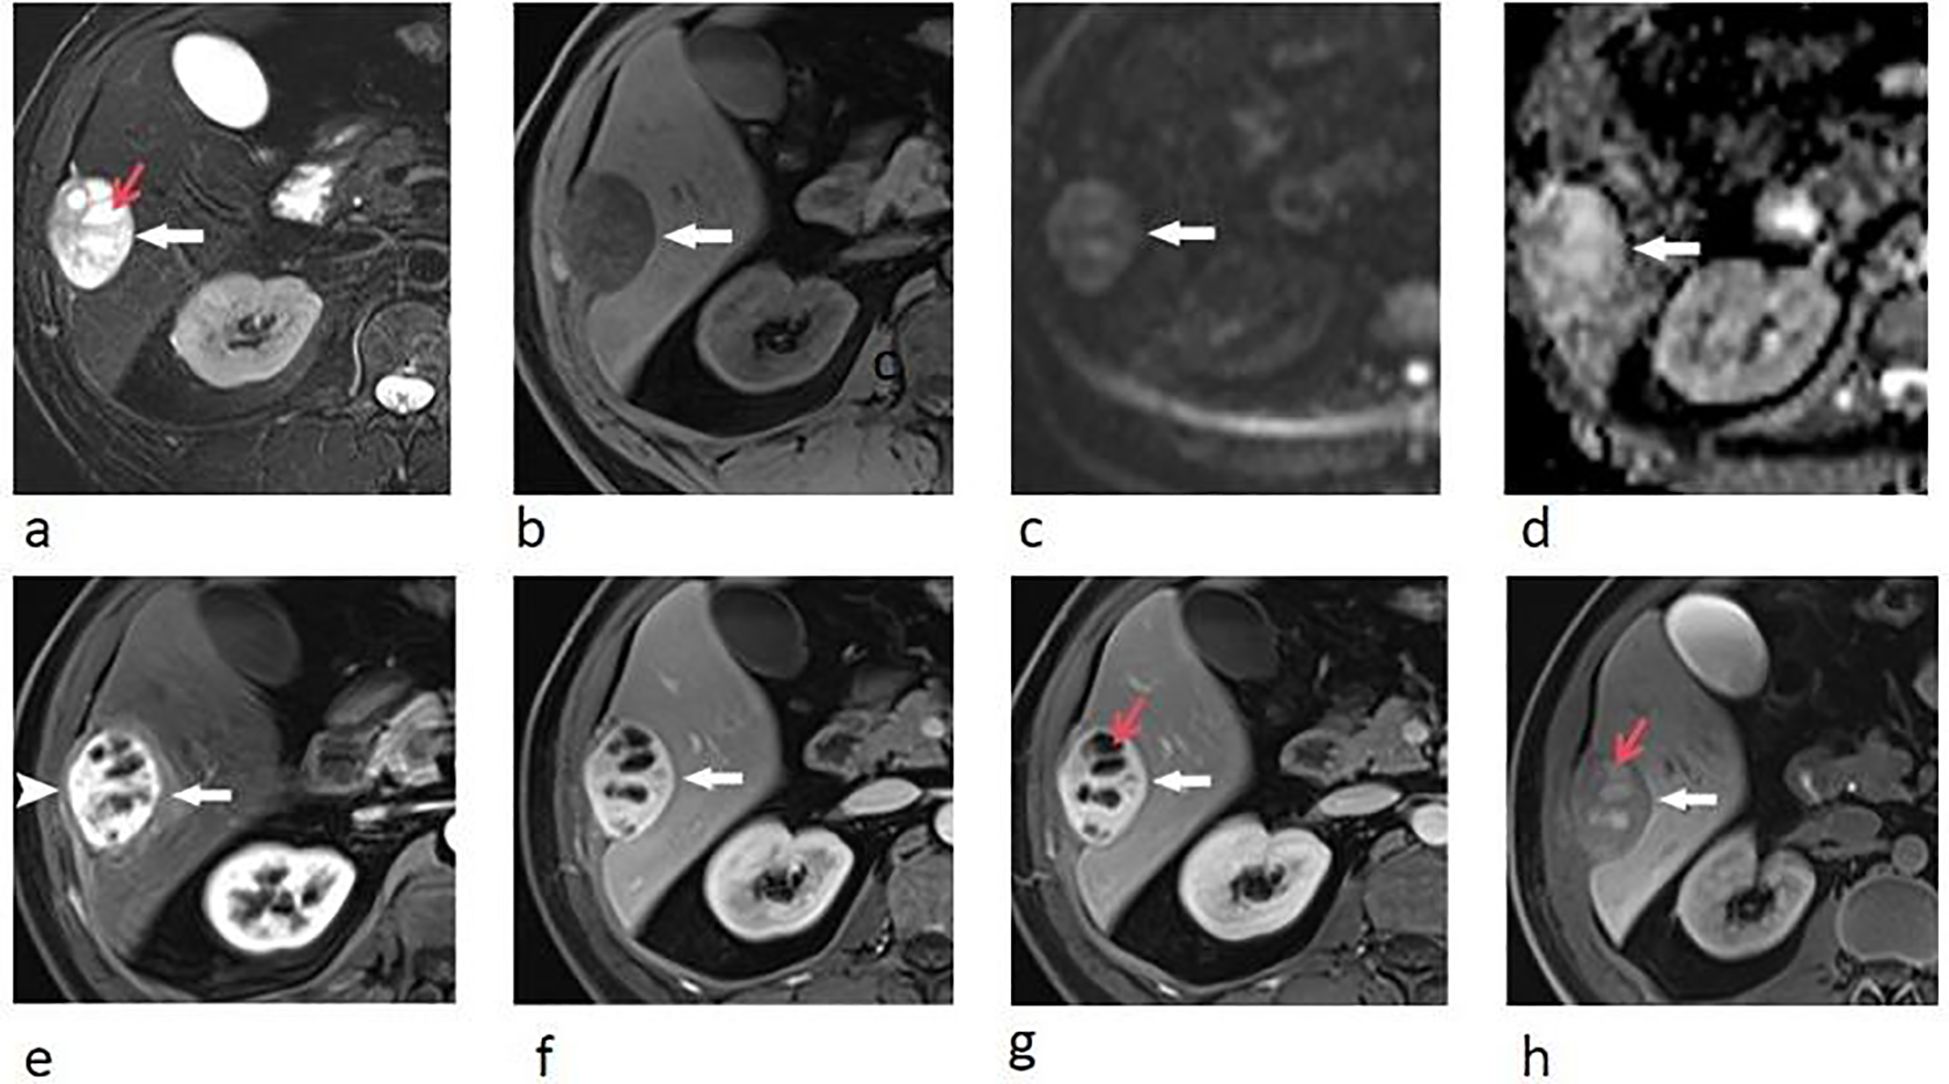

Upper abdominal MRI (3.0T, Magnetom Verio, Siemens, Germany) was subsequently performed. The large liver mass was heterogeneous on MR images, with hypointense on T1-weighted images and hyperintense on T2-weighted images. There were multi-lobulated, cystic areas within the mass. After injection of gadoxetic acid (Gd-BOPTA, MultiHance, Shanghai Bracco Sine Pharmaceutical, China), the mass showed inhomogeneous hyperintense in arterial phase and revealed prolonged enhancement in the portal venous phase and delayed phase (3 min). In hepatobiliary phase, the mass was hypointense with the cystic areas hyperintense. In addition, the liver capsule and the adjacent peritoneum also showed obvious enhancement (Figure 2). The nodule was hypointense on T1-weighted imaging and hyperintense on T2-weighted imaging. It revealed marked enhancement in arterial phase, and showed prolonged enhancement in portal venous phase and delayed phase (Figure 3).

Figure 2. Transverse breath-hold turbo spin-echo T2-weighted image (repetition time msec/echo time msec, 3000/104) (a) and fat-suppressed T1-weighted volume interpolated body examination (VIBE) image (repetition time msec/echo time msec, 3.92/1.39) (b) shows a well-circumscribed liver mass with intratumoral cystic areas (red arrow). Diffusion-weighted image (repetition time msec/echo time msec, 4000/73, b = 800 s/mm2) (c) and apparent diffusion coefficient (ADC) (d) map show that the water mobility of the mass was slightly restricted. The water mobility of intratumoral cystic areas was not restricted. Transverse enhanced VIBE images of arterial phase (e), portal venous phase (f), and delay phase (g) show marked and prolonged enhancement of the liver mass (arrows), with unenhanced intratumoral cystic areas (red arrow). The liver capsule also showed enhancement (arrow head). In hepatobiliary phase (h), the mass was hypointense compared with the liver parenchyma, with these cystic areas hyperintense (red arrow).